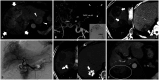

Yttrium-90 transarterial radioembolization (TARE) has emerged as a valuable treatment option for hepatocellular carcinoma (HCC) and is being increasingly incorporated into clinical guidelines. Recent advancements in dosimetry, including personalized dosimetry and multi-compartment modeling, have significantly improved tumor response and clinical outcomes. Although high tumor-absorbed doses are associated with better oncologic control, careful dose adjustment is essential for minimizing toxicity to normal liver tissue and lungs. This review explores the key aspects of TARE dosimetry, including single- and multi-compartment modeling, differences between resin and glass microspheres, dose-response relationships, and strategies to mitigate hepatotoxicity and radiation pneumonitis. Various clinical applications of TARE have been discussed, ranging from curative-intent radiation segmentectomy and lobectomy to palliative treatment of diffuse and macrovascular invasion-associated HCCs. In South Korea, where cadaveric liver transplantation is limited, a multidisciplinary approach is particularly important for optimizing treatment strategies and preserving liver function for potential future interventions. As dosimetry continues to evolve, further research is required to refine dose optimization protocols and validate their clinical impact in different patient populations, including those in South Korea.